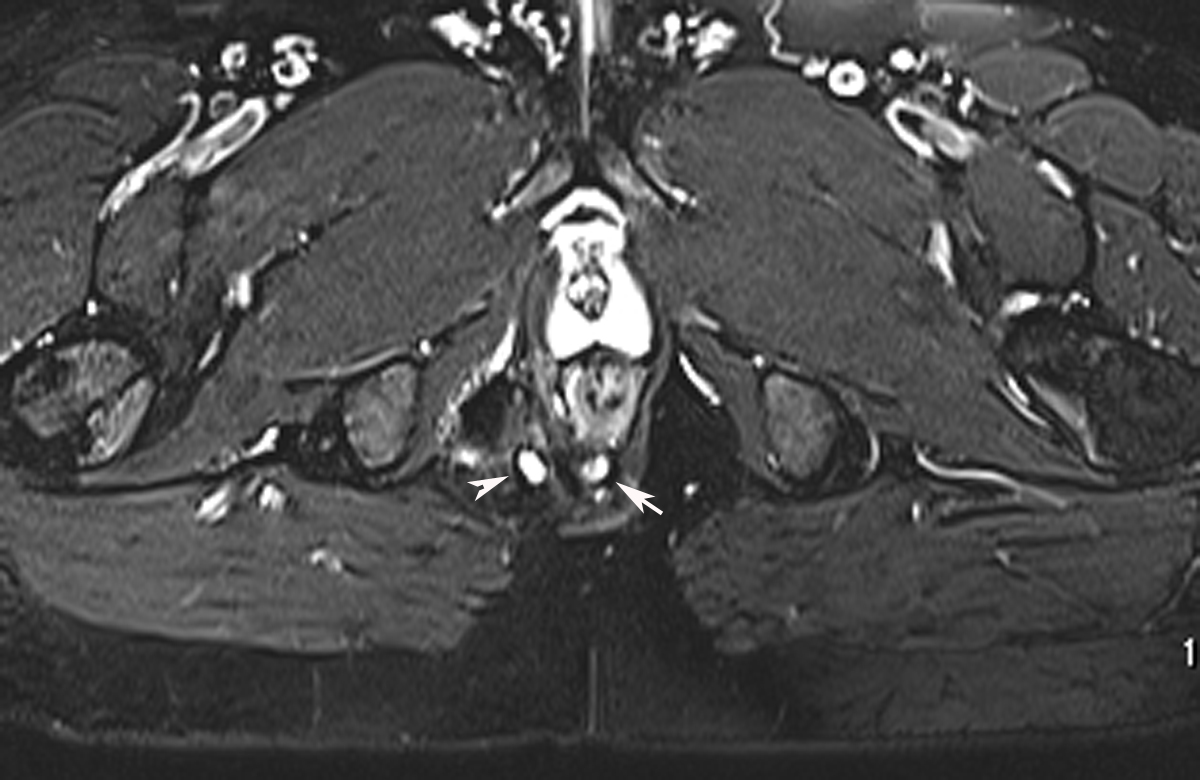

From manju-imagingxpert.blogspot.com

Radiodiagnosis Imaging is AmazingInteresting cases Perianal Fistula Common Fistula Sites the three most common avfs are the radiocephalic fistula, the brachiocephalic fistula, and the brachial. an arteriovenous fistula is when an artery and vein connect directly, allowing blood to flow incorrectly. Usually, blood flows from the arteries to tiny. an arteriovenous (av) fistula is an irregular connection between an artery and a vein. acquired avf of. Common Fistula Sites.

Radiodiagnosis Imaging is AmazingInteresting cases Perianal Fistula Common Fistula Sites an arteriovenous fistula is when an artery and vein connect directly, allowing blood to flow incorrectly. proximal fistulas are associated with a higher rate of complications than distal fistula creations. arteriovenous fistulas (avfs) are abnormal connections between an artery and a vein (see image. the most common arteriovenous fistula is intentional: acquired avf of the. Common Fistula Sites.